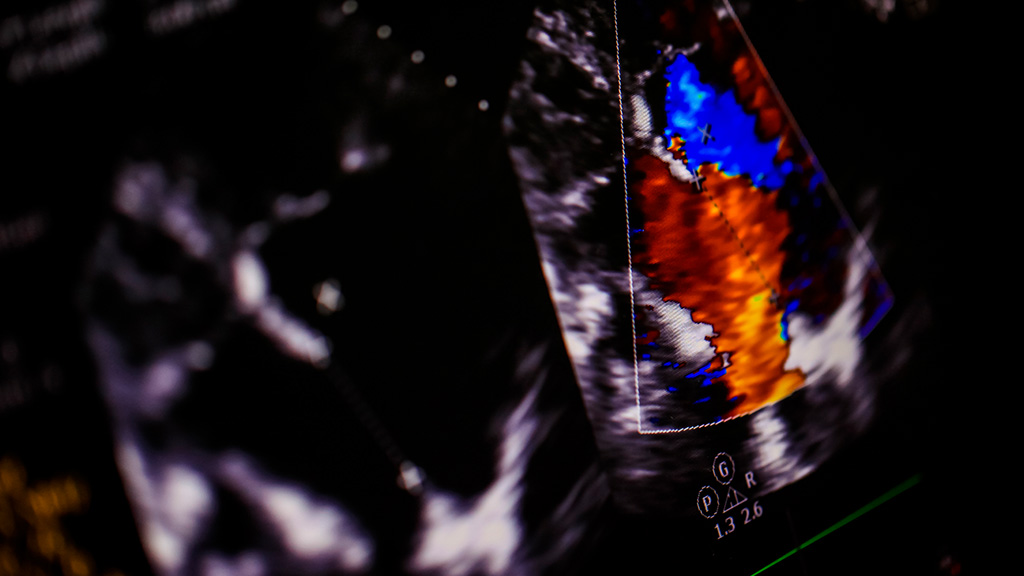

Ultrasonido Doppler Color Utero y Ov.(Suprapúbico)